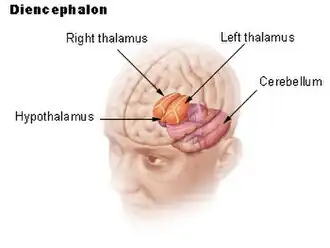

Diencephalon

The hypothalamus and the right and left halves of the thalamus are labeled. The cerebellum is not part of the diencephalon. | |

In the human brain, the diencephalon (or interbrain[1]) is a division of the forebrain (embryonic prosencephalon). It is situated between the telencephalon and the midbrain (embryonic mesencephalon). The diencephalon has also been known as the tweenbrain in older literature.[2] It consists of structures that are on either side of the third ventricle, including the thalamus, the hypothalamus, the epithalamus and the subthalamus.

The diencephalon consists of the following structures:

- Thalamus

- Hypothalamus including the posterior pituitary

- Epithalamus which consists of:

The diencephalon is the region of the embryonic vertebrate neural tube that gives rise to anterior forebrain structures including the thalamus, hypothalamus, posterior portion of the pituitary gland, and the pineal gland. The diencephalon encloses a cavity called the third ventricle. The thalamus serves as a relay centre for sensory and motor impulses between the spinal cord and medulla oblongata, and the cerebrum. It recognizes sensory impulses of heat, cold, pain, pressure etc. The floor of the third ventricle is called the hypothalamus. It has control centres for control of eye movement and hearing responses.